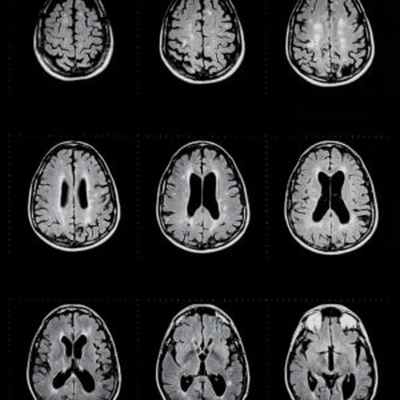

Стеноз водопровода головного мозга на МРТ

• Вентрикуломегалия (боковые и третий желудочки) на фоне нормальных размеров четвертого желудочка

• ± перивентрикулярный интерстициальный отек (некомпенсированная гидроцефалия)

• Мультипланарная МРТ с получением сагиттальных 3D сильно взвешенных Т2-ВИ и кино-MPT с кардиосинхронизацией в сагиттальной плоскости

(Слева) На рисунке сагиттального среза показана обструктивная гидроцефалия с заметным увеличением боковых и III желудочков, растяжение (истончение) мозолистого тела и воронкообразное сужение сильвиева водопровода, обусловленное дистальной обструкцией. Обратите внимание на нормальные размеры IVжелудочка и грыжевое выпячивание дна III желудочка вследствие гидроцефалии.

(Справа) МРТ, постконтрастное Т1-ВИ, сагиттальный срез: в сильвиевом водопроводе определяется перепонка, вызывающая расширение проксимальных отделов сильвиева водопровода, расширение боковых и III желудочков. Четвертый желудочек в норме. (Слева) МРТ, Т2-ВИ SPACE, сагиттальный срез: нормальный участок потери сигнала за счет эффекта потока, обусловленный ликворотоком из III желудочка в IV желудочек.

(Справа) МРТ, Т2-ВИ SPACE, сагиттальный срез: классические признаки стеноза сильвиева водопровода. Визуализируются воронкообразная форма расширенного сильвиева водопровода, а также расширение боковых и III желудочков в сочетании с истончением и прогибом кверху мозолистого тела. Обратите внимание на нормальные размеры IV желудочка.

Признаки стеноза водопровода, отличные от упомянутых в разделе «Причины стеноза», включают обнаружение увеличенного бокового и третьего желудочка в сочетании с меньшим четвертым желудочком. Это изменение размера желудочка указывает на закупорку водопровода, поскольку он находится между третьим и четвертым желудочками. Еще один признак стеноза - деформация среднего мозга, которая может быть серьезной. Это вызвано градиентом давления, образовавшимся из-за закупорки водопровода.